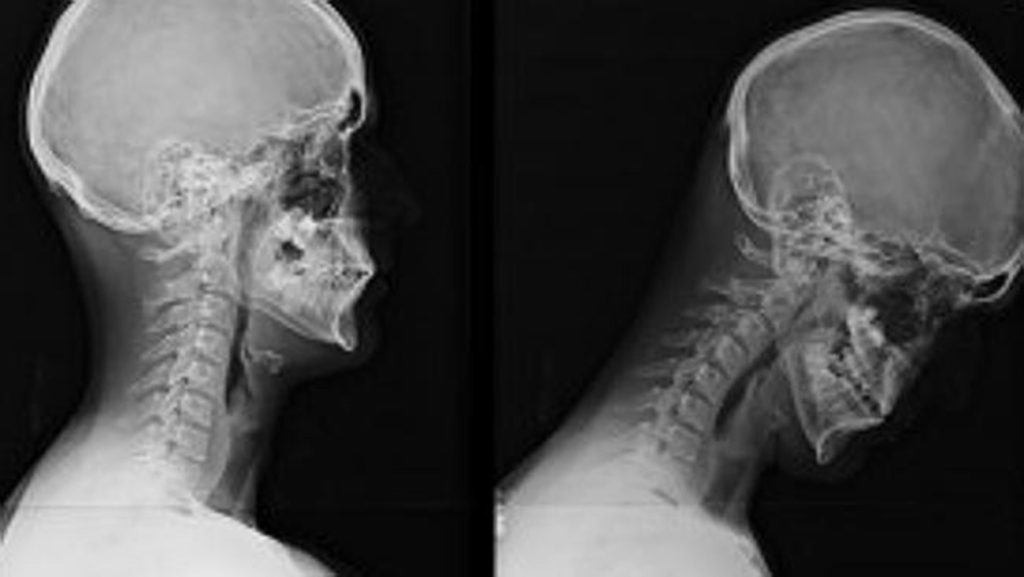

What Is Tech Neck Syndrome . these muscles can get overly tired and sore from looking down at our smartphones, computers, or tablets all day. It can cause back and shoulder pain, headaches, and other. what is tech neck? tech neck is a term used to describe chronic neck pain caused by continuously straining the neck muscles while using technology—electronic devices like phones, tablets, and. “text neck syndrome” (or, “tech neck”) occurs when your neck muscles strain to hold your head up as you look. tech neck is any form of chronic neck or shoulder pain, soreness, or stiffness caused by poor posture while using technology such as. Tech neck is any form of chronic neck or shoulder pain, soreness or stiffness caused by poor posture while using technology,. That’s what we call tech neck. Headaches, stiff necks, neck spasms, and ‘tech neck’ is the result of looking down at a phone or other screen for too long. What are the symptoms of tech neck? text neck (or tech neck) is a syndrome that happens after a repeated amount of stress occurs in our neck area due to having our heads in a.